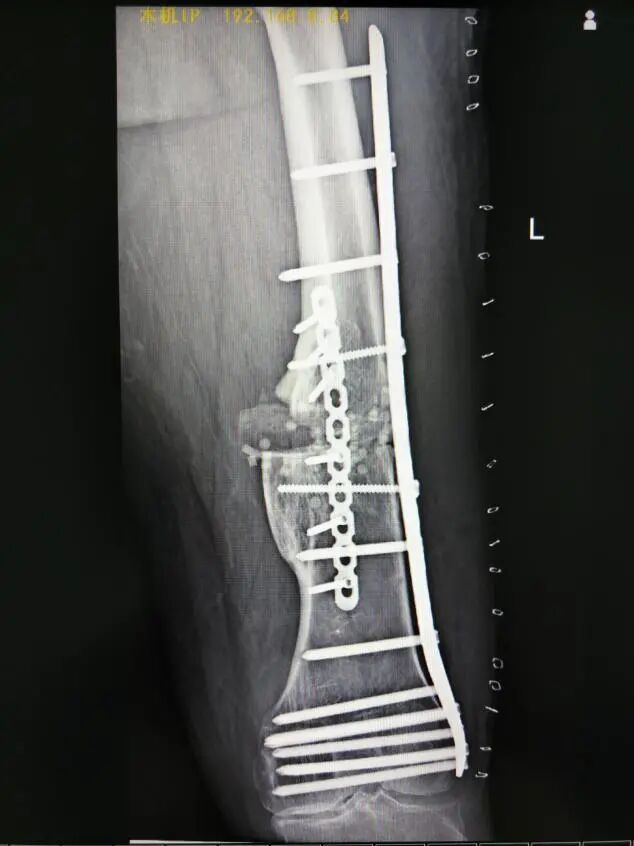

術(shù)前X線片(內(nèi)翻成角30°)

術(shù)前X線片(向后成角17°)

術(shù)后復(fù)查X線片影像(正位)

術(shù)后復(fù)查X線片影像(側(cè)位)